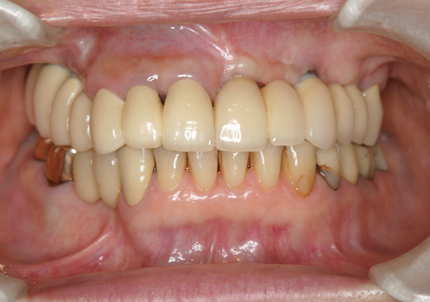

1.初診時口腔内(2007年6月30日)

8.初診より現在に至る

強い歯ぎしり、くいしばりで奥歯の歯牙破折、深い虫歯で保存不可能となり全顎治療となる。

↑ 2007年6月30日(初診)

↑ 2025年9月9日

治療後は経過良好